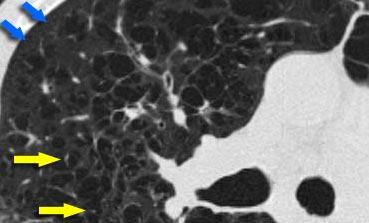

Suy giảm hệ số hấp thụ dạng khảm trong Viêm phổi quá mẫn

Hình ảnh bên trái cho thấy bệnh nhân có hình ảnh kính mờ phân bố dạng khảm. Một số tiểu thùy bị tổn thương, trong khi các tiểu thùy khác không bị ảnh hưởng.

Chẩn đoán phân biệt bao gồm viêm phổi quá mẫn (HP), viêm tiểu phế quản hoặc bệnh huyết khối tắc mạch.

Tiền sử lâm sàng điển hình của viêm phổi quá mẫn.

HP thường biểu hiện với các nốt trung tiểu thùy có tỷ trọng kính mờ (nốt acinar).

Khi hợp lưu, HRCT cho thấy hình ảnh kính mờ lan tỏa.

HP là bệnh phổi dị ứng do hít phải các kháng nguyên có trong nhiều loại bụi hữu cơ.

Phổi nông dân, hội chứng HP được biết đến nhiều nhất, xảy ra do hít phải các vi nấm trong cỏ khô ẩm hoặc tiếp xúc với chim cảnh.

HP typically manifests in two forms:

- Mờ kính mờ phân bố dạng khảm (như trong trường hợp này).

- Các nốt centrilobular có mật độ kính mờ (nốt acinar).